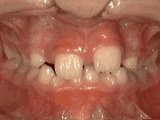

以下几种类型为典型的牙齿畸形症状,比如乳牙早失引起的前牙移位、牙齿错乱、牙列拥挤、上下牙齿开郃、深覆合、牙齿稀疏、前牙反颌地包天等,有的牙齿畸形还会导致脸型发育问题,出现小鸟嘴、弯月脸、短下巴、歪下巴、左右脸不对症等现象。

前牙移位多由于乳牙过早缺失导致,多因乳牙龋坏不及时治疗、意外断折引起。

牙齿错乱表现为多生牙、牙床过小等造成,严重的拥挤错乱一般需要拔牙,给余牙移动的空间。

牙列拥挤主要常见牙齿过多,牙槽骨过窄,导致牙齿没有足够空间,一般根据检查结果,除了拔牙还有片切、扩弓、推磨牙远移等方法,不见得一定要拔牙。